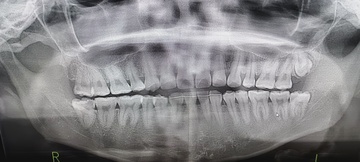

Before(下親知らずの抜歯前) 虫歯のある状態で埋まっている親知らず 抜歯前の骨の状態のレントゲン像

After(下親知らずの抜歯後) 横に生えた状態で埋まっている親知らずの抜歯後 虫歯がある親知らずの抜歯後 抜歯後の骨の状態のレントゲン像

原因をより詳しく調べるためパノラマレントゲンを撮影したところ、右下の親知らずは骨の中に埋まった状態のまま虫歯になり、隣接する歯を押しており、接触している奥歯の骨が溶けてしまっています。 そのため、右下の親知らずと隣の奥歯の間には、歯と歯ぐきの境目の溝である「歯周ポケット」が通常よりもかなり深くなっていました。

まず、親知らずと骨の中にある神経の位置、歯や周囲の骨の詳細な情報を確認するために、歯科用パノラマデジタル写真で口腔内を撮影します。撮影結果を踏まえ、抜歯方法や施術の難易度をしっかり確認しました。